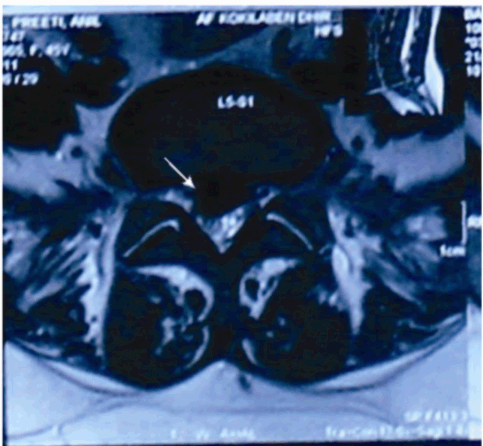

An MRI was done, that showed diffuse disc bulge at L5-S1 level with an inferiorly migrated central extrusion causing severe compression of the thecal sac (Figure 1, 2). It also revealed an intradural, extramedullary, cystic space occupying lesion with an internal solid-cystic nodule, extending from L1 to L2-3 causing compression and anterior displacement of filum and cauda equina (Figure 1). The lesion showed signal intensities similar to those of CSF on T1, T2 and FLAIR images. There was no enhancement noted after administration of contrast in the MR scans. The imaging features were suggestive of a benign cyst with possibilities of a cysticercosis or an arachnoid cyst.

Figure 2: T2 weighted MR film showing diffuse disc bulge at L5-S1 level with an inferiorly migrated central extrusion causing severe compression of the thecal sac.